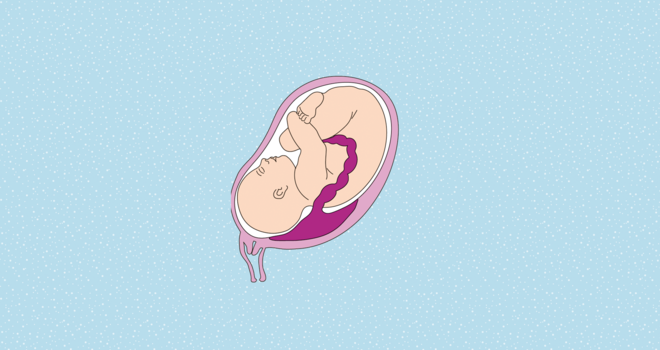

Wie sich ein Fehlsitz der Plazenta auf den weiteren Verlauf der Schwangerschaft und auch auf die Geburt auswirkt, hängt davon ab, wo genau die Plazenta in der Gebärmutter liegt. Zu unterscheiden sind:

- Placenta praevia totalis: Die Plazenta liegt direkt über dem Ausgang der Gebärmutter.

- Placenta praevia partialis: Der innere Muttermund ist teilweise vom Mutterkuchen überdeckt.

- Placenta praevia marginalis: Die Plazenta grenzt an den Rand des inneren Muttermundes.

Wo sitzt die Plazenta?

Die Lage des Mutterkuchens hat großen Einfluss darauf, ob ein Kind per Kaiserschnitt geholt werden muss. Je tiefer die Plazenta liegt, umso wahrscheinlicher ist der Eingriff

Selbst wenn die Plazenta nur teilweise über den inneren Gebärmuttermund gewachsen ist, besteht bereits eine hohe Gefahr, dass es vor dem Beginn der Wehen zu schwersten Blutungen kommt. "Eine natürliche Geburt wäre zu gefährlich, in diesen Fällen wird immer ein Kaiserschnitt geplant", erklärt Albring.

Im Fall einer Placenta praevia totalis und partialis ist eine Spontangeburt also ausgeschlossen. Bei einer natürlichen Geburt würde sich die Plazenta als Erstes lösen, das Kind bekäme keinen Sauerstoff mehr. Auch die Mutter wäre in Gefahr. "Mit großer Wahrscheinlichkeit würden unstillbare, starke Blutungen auftreten, die nur durch eine notfallmäßige Entfernung der gesamten Gebärmutter gestillt werden könnten", so Albring.

Grenzt die Plazenta hingegen nur an den Rand des Muttermunds, schließt ihn aber nicht mit ein, kann eine natürliche Geburt unter bestimmten Bedingungen möglich sein. "Der Arzt stellt per Ultraschall sicher, dass die Plazenta weit genug vom Muttermund entfernt liegt und durch die Dehnung der Gebärmutter bei der Geburt nicht reißen wird", sagt Albring. Gynäkologe und Hebamme empfehlen jedoch, unbedingt in einer Klinik zu entbinden, damit im Notfall schnell reagiert werden kann.